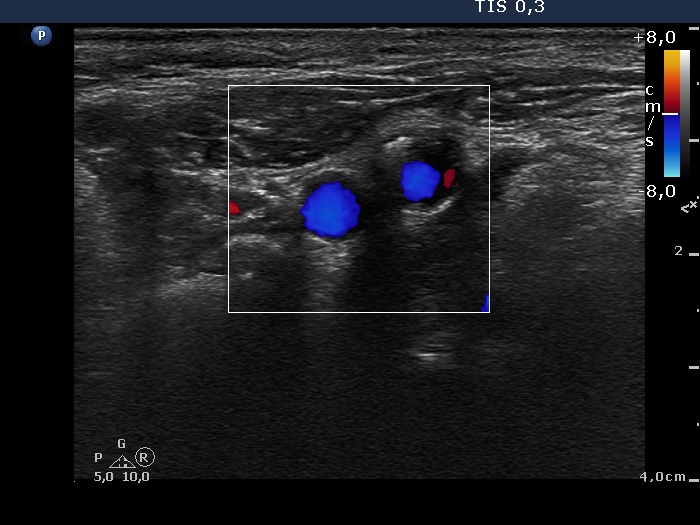

Thyroid cancers - case 529 (ultrasonographic picture 10)

Lateral to the left lobe, transverse view, color Doppler mode. There is a large vessel within the node.